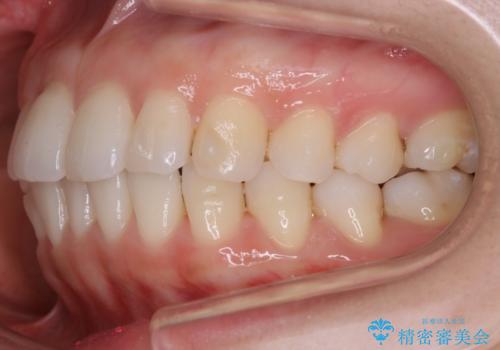

【非抜歯】前歯のガタつき マウスピースの部分矯正

- 上下の前歯の細かいガタつきの治療をご希望されて来院されました。

奥歯部分にはガタつきや噛み合わせの問題などがほとんど見られず、前歯のガタつきも軽度だったため、インビザライン ライト パッケージでの部分矯正を行うこととなりました。

今回のケースでは奥歯の噛み合わせに問題がほぼみられなかったため、前歯の位置のみに焦点を当て部分矯正を行いました。

適応されるケースが限られるものの、適応であった場合の治療期間は全体矯正と比べると格段に短くなり、費用も抑えられます。